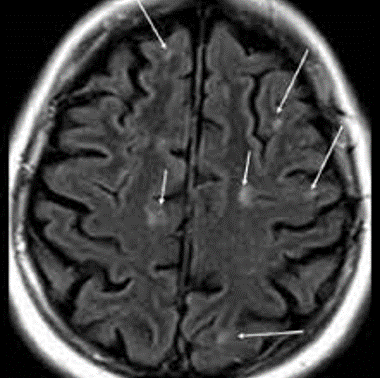

MRI brain

A

Diagnostic image of choice

Hyperintense white matter lesions on T2 sequence

Plaques

Ring enhancing

Ovoid

“Black hole” lesions

Severe demyelination and axonal loss